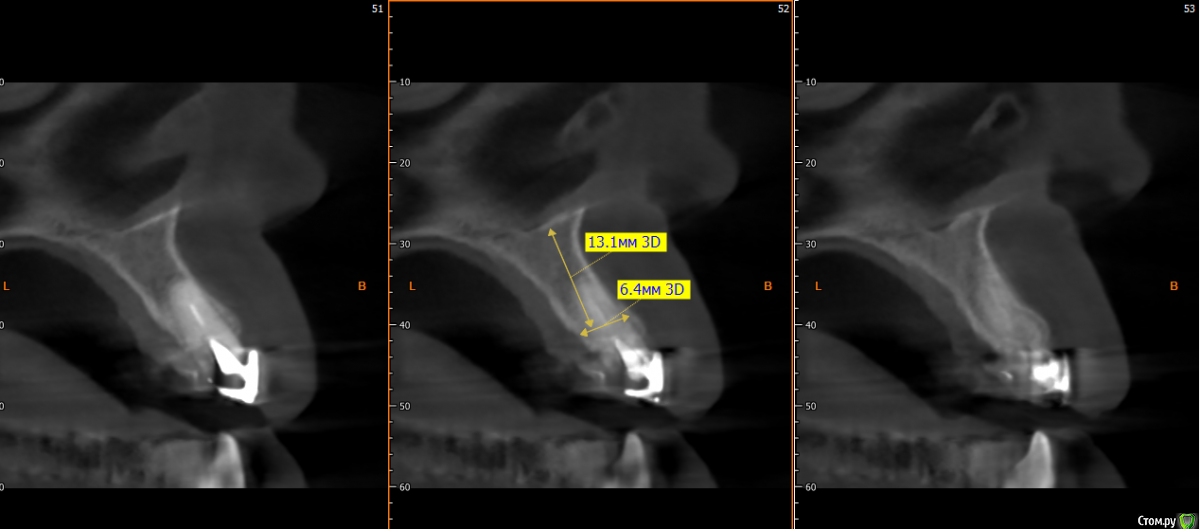

kramer Опубликовано 15 мая, 2019 Поделиться Опубликовано 15 мая, 2019 Коллеги, здравствуйте. Нужен совет. Ситуация: пациентка 70 лет (родственница), давно носила бюгельный протез, и вот одному из опорных зубов пришел конец. КТ ниже, фотографии завтра добавлю. Рассматриваю вариант изготовления несъемного протеза на 4 имплантатах. Опыта все-на-4 нет. Поэтому хотелось бы по крайней мере собрать информацию, возможна ли такая опция. Особенно волнует 2 момента: 1) Отсутствует вертикальная атрофия альвеолярного отростка во фронтальном отделе. Линия улыбки низкая. Предположим, окончательный протез будет м\к или циркон. Означает ли это, что редукцию кости делать необязательно? (правда там и редуцировать особо некуда). 2) В области 14 и 24 ширина гребня 3,5-4 мм. Что делать с этим? Оставлять пришеечную часть винта не покрытым костью небно или пытаться каким-то образом конденсировать кость? 14122224 Ссылка на комментарий

Smileee Опубликовано 16 мая, 2019 Поделиться Опубликовано 16 мая, 2019 Я бы везде установил 3.5, в области 24 немного редуцировал бы кость по вертикали. Все импланты максимально небно. Ссылка на комментарий

kramer Опубликовано 17 мая, 2019 Автор Поделиться Опубликовано 17 мая, 2019 не надо там ничего редуцировать, само резорбируется после удаления на 1-2 мм. все на 4-х и счастья вашей родственницеСпасибо, что делать с узким гребнем? Максимально глубить? Ссылка на комментарий